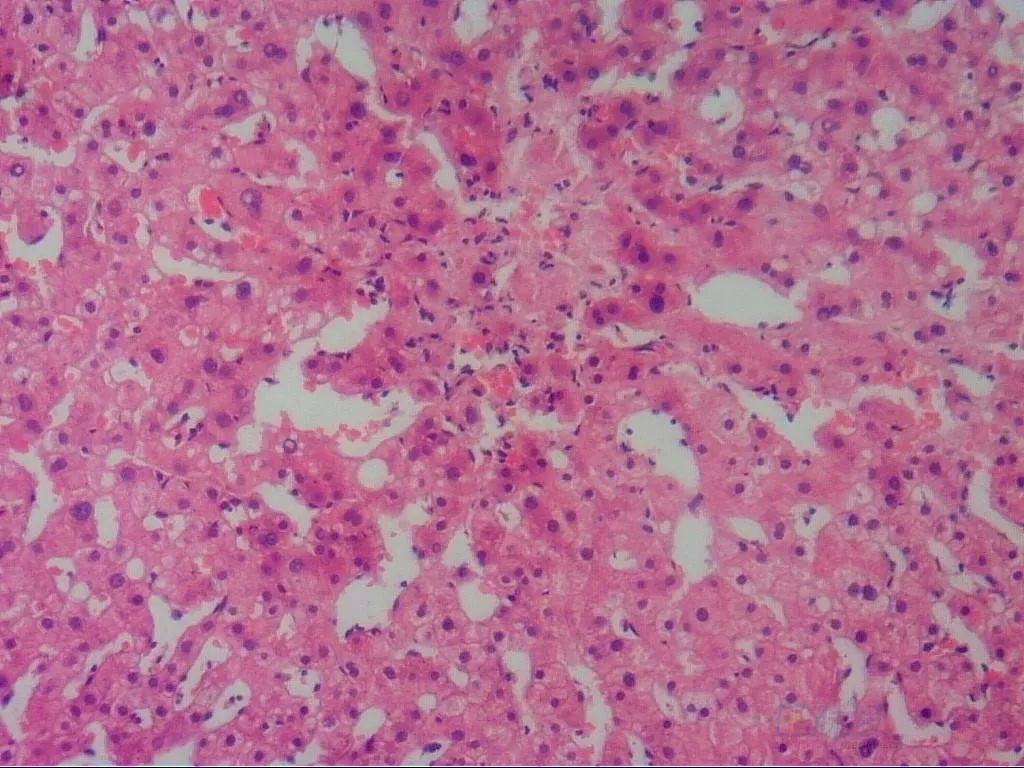

患者经过抗凝治疗,病情得到控制,基本治愈。三个月后,我们再次做肝穿刺病理学检查(见图4)。根据病理表现,发现继续抗凝治疗已经难以改善中央静脉闭塞,因此停用抗凝药物。

图4 病理解读:肝细胞无明显坏死、炎症,少数中央区可见淤血表现,有2条中央静脉已经闭塞,周围肝窦扩张,个别汇管区出现纤维化扩大,形成多个门静脉分支,胆管、动脉无异常表现,病理为HSOS/HVOD治愈后表现

HSOS的病理典型表现:以肝腺泡Ⅲ区为主的肝窦内皮细胞肿胀、损伤、脱落,肝窦显著扩张充血;肝细胞不同程度的肿胀、坏死,红细胞渗入狄氏间隙,肝内小静脉管壁增厚,管腔狭窄、闭塞,无纤维化表现或可见汇管区轻度纤维增生。